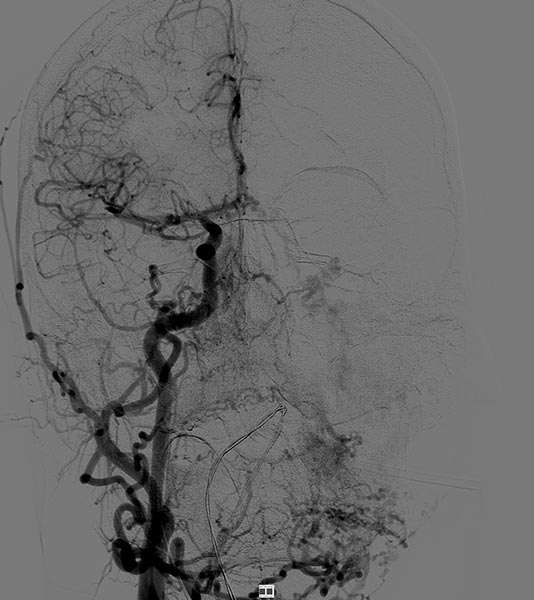

Lateral view of a digital subtraction angiography after contrast injection into the left external carotid artery. The AVM is visible as a diffuse, reticular net-like nidus with direct, strong venous outflow centrally in the left cheek (fast-flow malformation).

Lateral view, DSA after contrast injection in the left internal carotid artery. There is also a massive supply to the nidus of the AVM from the internal carotid artery, mainly via the ophthalmic artery and the meningohypophyseal trunk.

This complicates embolization therapy considerably.